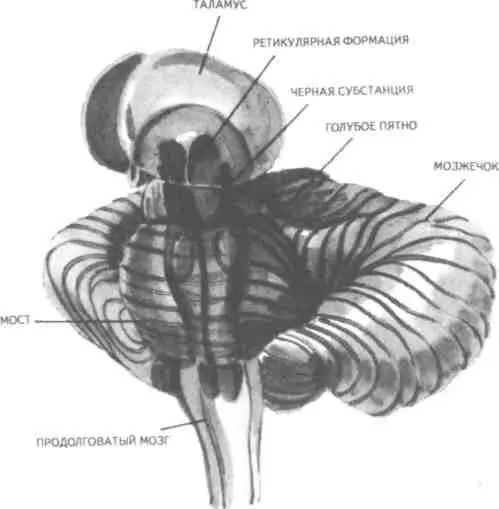

Анатомо-фи-зиологической основой низших или простейших эмоций являются лимбические

структуры ц.н.с, а также процессы, происходящие в таламусе и гипоталамусе (рис. 24, 25).

Рис. 24. Важнейшие части мозга, образующие лимбическую систему. Можно видеть, что они

располагаются вдоль краев больших полушарий, как бы «окаймляют» их